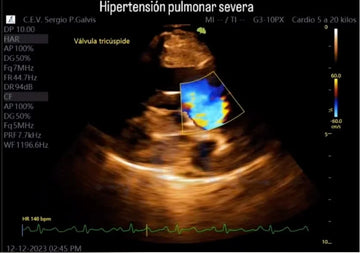

In veterinary medicine, ultrasound scans are essential for identifying various health conditions in animals. The image shown is an abdominal ultrasound that provides important details about the animal's internal structures. As in human medicine, this technique allows veterinarians to visualize organs such as the kidneys, liver, intestines, and other abdominal organs.

In this ultrasound, we observe an abdominal structure in a transverse plane. Images like these allow us to study:

Image clarity is essential for the veterinarian to assess whether the organs are of normal size and if any abnormalities are present. In the provided image, the structures observed appear to indicate a routine abdominal examination, but their interpretation will depend on the patient's clinical history.